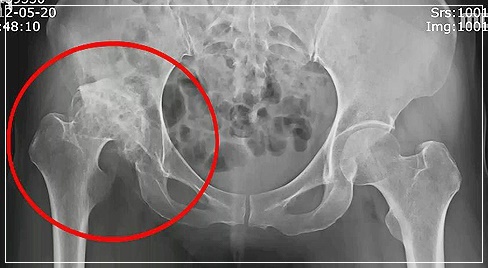

고관절 통증은 통증 자체로 보면 자칫 허리 디스크 질환과 혼동될 수도 있는데 그 이유는 고관절 자체가 다른 부위와는 달리 신체의 깊숙한곳에 있는데다 통증 부위 또한 정확하지 않기 때문입니다. 갑작스럽게 통증이 찾아오기 때문에 대수롭지 않게 여기고 넘겨서 병을 키우는 경우가 많습니다. 특히 이미 퇴행성 진행이 되고 있는 환자의 경우 방치하면 퇴행성 고관절염으로 악화될 수 있습니다.

고관절 통증 치료는 초기 환자들은 약물 치료나 관절 내시경을 통해 충분히치료가 가능하지만 통증이 너무 심해 거동이 불편한 말기의 환자들은 고관절 인공관절 수술과 재활치료를 통한 치료가 요구됩니다. 고관절은 통증이 시작되는 초기부터 정확한 진단이 바탕이 되어야 증상에 적합한 맞춤형 치료로 빠른 회복이 가능합니다.